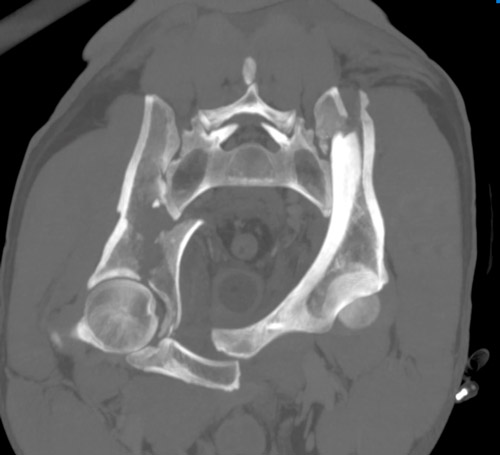

Emergency CT-scan with overthigthened binder

Emergency CT scan